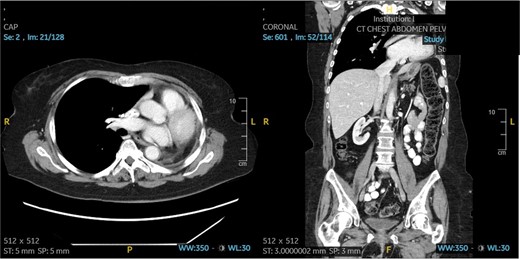

A 60-year-old woman with acute lymphoblastic leukemia recently started on chemotherapy presented to the emergency department with a dry cough that later progressed to a productive cough with green sputum. Exam was largely unremarkable as patient was afebrile and had normal lung auscultation. Initial infectious work-up, including bacterial, fungal and mycobacterial cultures, fungal serum and urine antigens, and COVID-19 testing were negative. Given a negative infectious work-up, a CT chest, abdomen, and pelvis was obtained revealing a 5 cm perihilar mass causing complete obliteration of the left pulmonary artery and minimal-to-no perfusion to the left lung (Fig. 2).

Patient 2 pre-operative images. (A) Coronal section of CT angiogram showing LUL mass abutting the aortic arch and invading the left main pulmonary artery and left mainstem bronchus. (B) Axial CTA showing complete occlusion of the left pulmonary artery. (C) 3D reconstruction of CTA showing complete occlusion of the left pulmonary artery and lack of opacification of any pulmonary artery branches and pulmonary oligemia.

A bronchoscopy was completed for biopsy of the lesion and revealed angioinvasive mucormycosis. The patient was immediately started on amphotericin and isavuconazole and evaluated by thoracic surgery for possible surgical resection. Given the perihilar location involving the pulmonary artery, it was likely that a pneumonectomy would be required. Pulmonary function tests (PFTs) were completed and showed an FEV1 of 54% predicted and diffusing capacity of the lungs for carbon monoxide (DLCO) of 57% predicted. Although these PFTs alone suggest that a pneumonectomy may not be tolerated; it is important to note that on the CT scan there was no perfusion to the left lung. A V/Q scan confirmed absent perfusion to the left lung given the invasion of the pulmonary artery with only 3.4% of perfusion reaching the left lung. Therefore, a pneumonectomy would not change PFTs significantly.